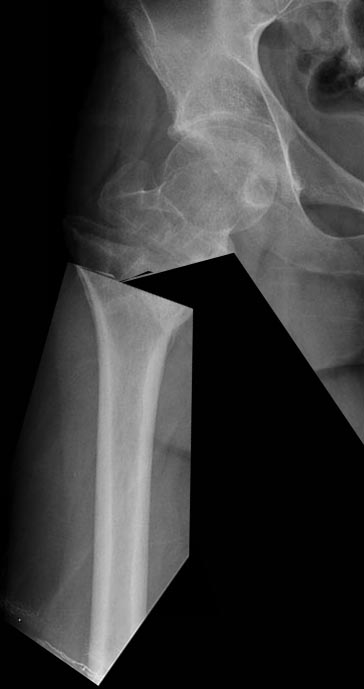

Re: Перелом проксимального отдела бедра

Если головка хорошая, то по линии перелома, если плохая- эндопротез.

С головкой тут с подавляющей вероятностью все в порядке. По линии перелома разобщить можно, но делать это, потом добиваться восстановления шеечно-диафизарного угла может быть труднее и кровавее, чем сделать чрескожную остеотомию на уровне интактной кости, и закрыто зафиксировать гвоздем.